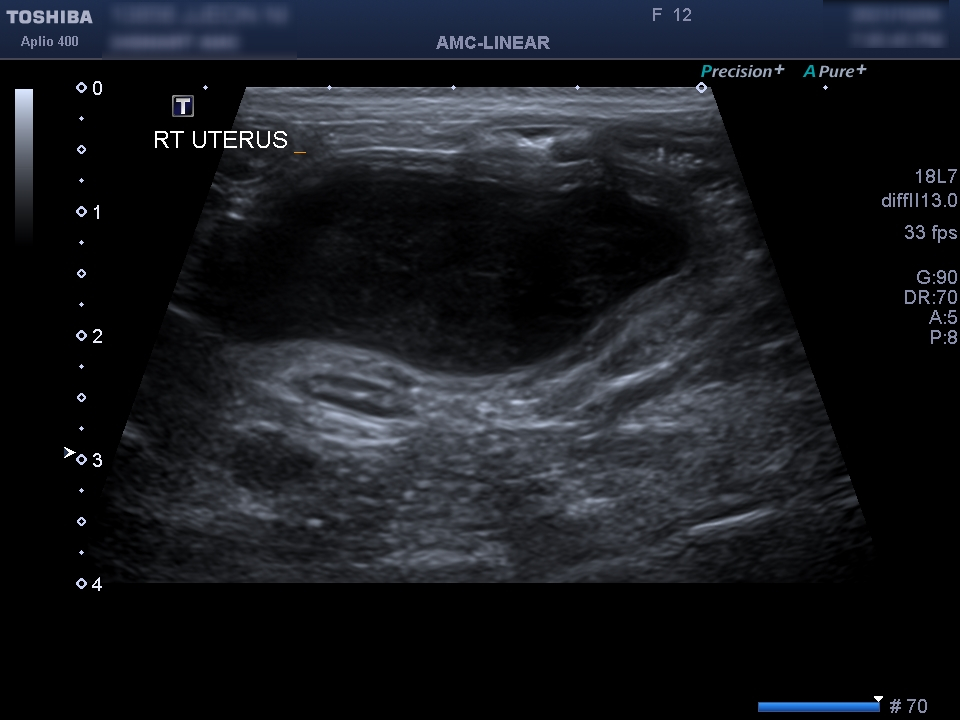

동물 병원에 내원해 주시고, 수의사의 판단으로 검사를 통해 확인이 됩니다.기본적으로 필요한 최소한의 검사는 복부 초음파 검사나 X 선 검사, 혈액 검사 등이 진단에 필요합니다.

신체 검사 결과 생식기 쪽에서 삼출물이 확인되었습니다.자궁 축농이 의심되는 상황이어서 초음파 검사를 통해 확진을 할 수 있었습니다.

초음파 검사를 통해 확장되어 있던 양쪽 자궁을 확인할 수 있었습니다